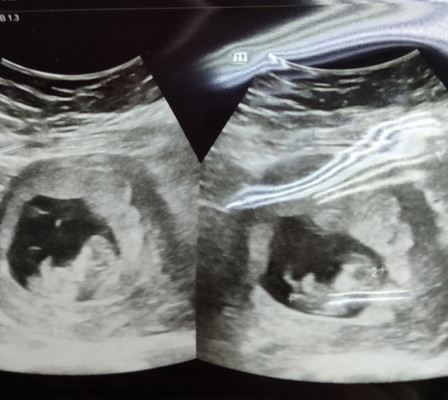

Kembar ke x?

Hai..nk tanye kalo gmbr scan kite ade dua mcmni maksudnye kite mengandung kembar ke..?sbb dokte xckp pape plak..kandungan baru 10minggu..tp adk bradik sume kate kembar..maafla xtau,first beby..#ingintahu #firstbaby #pleasehelp #seriusnanya